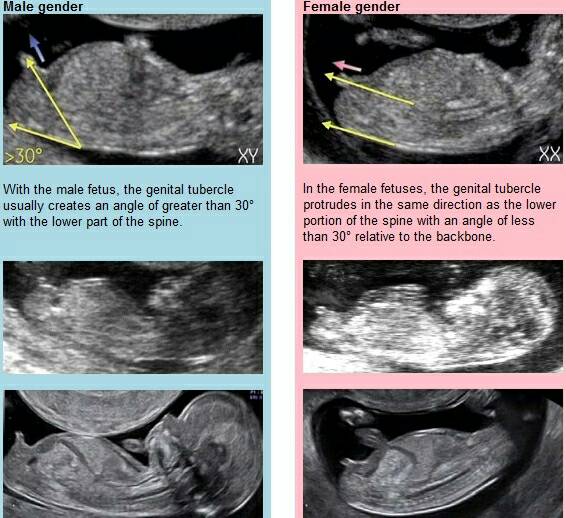

Chłopiec jak się patrzy hihi [emoji23]

Mój bąbelek, zdjęcie z piątku, całe 7cmPodobno chłopiec ale 100%pewności nie ma....

To kolano akuratChłopiec jak się patrzy hihi [emoji23]